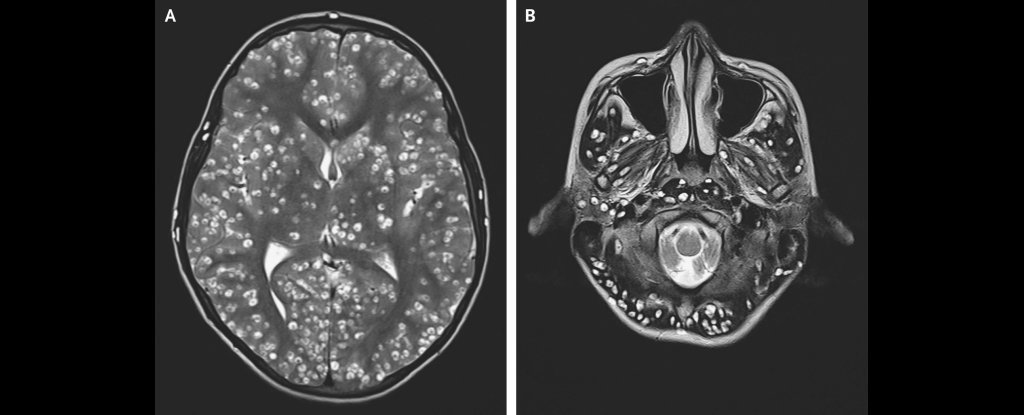

Une autopsie sera effectuée notamment sur son cerveau car celui-ci révèlera beaucoup d'anomalies. Mais étrangement, celui-ci aurait disparu du jour au lendemain sans laisser de traces.